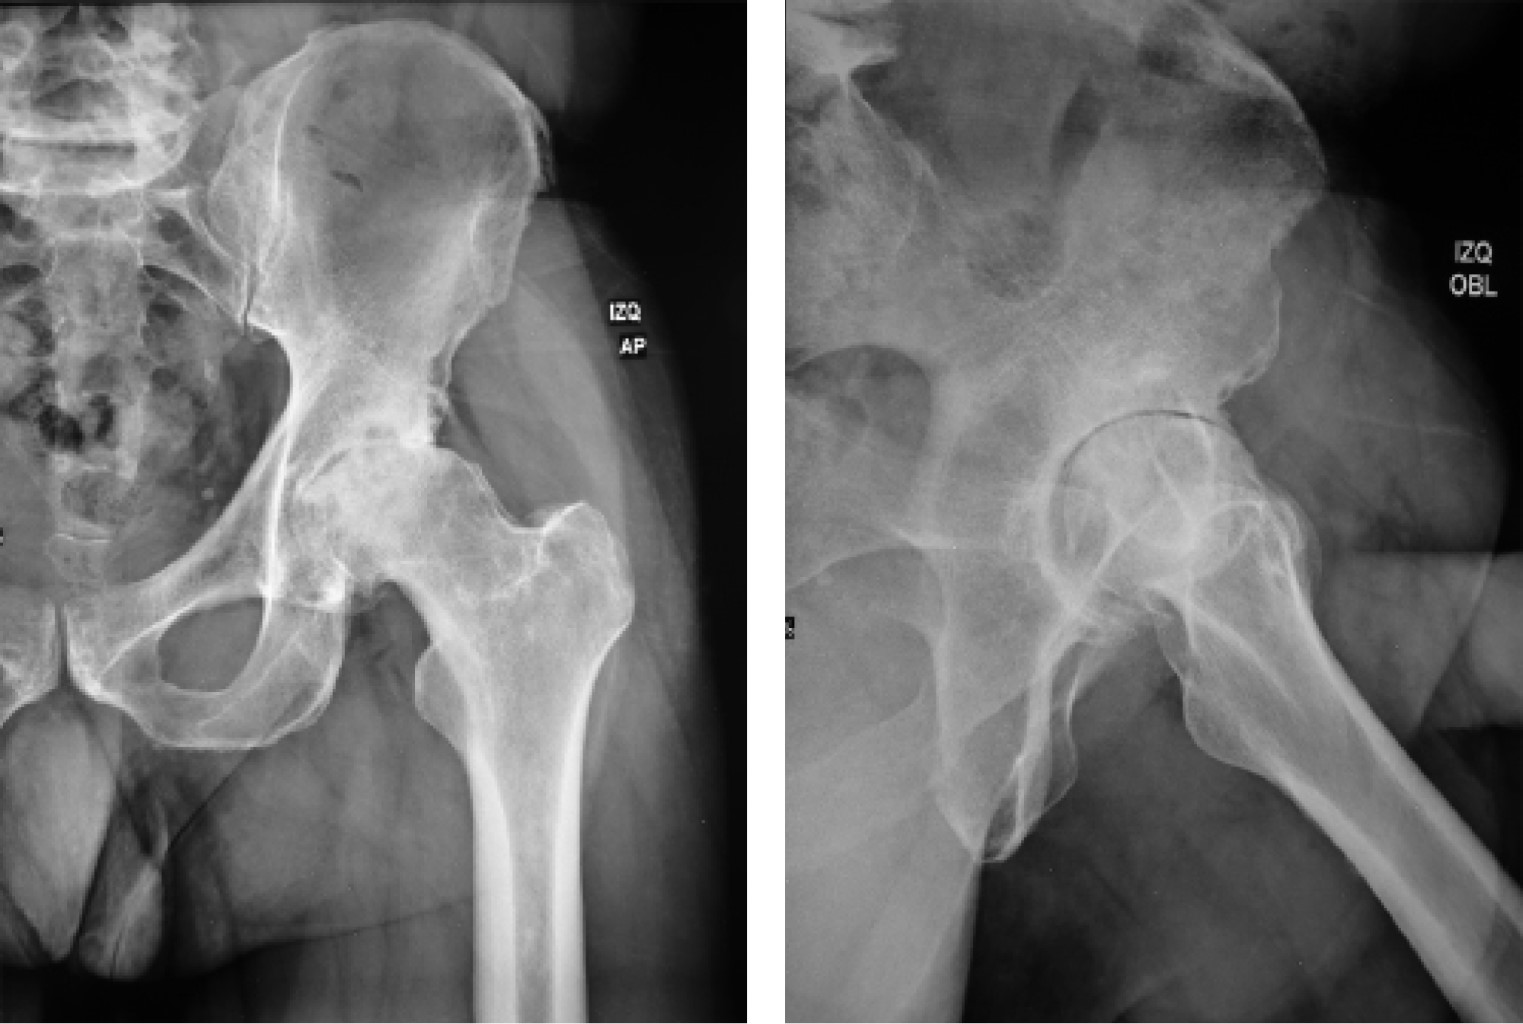

Previa aprobación por los Comités de Investigación y de Ética en Investigación de este hospital (Centro Médico ABC), se efectuó un estudio retrospectivo de todos aquellos casos consecutivos de artroplastía total de cadera, entre Abril de 2018 y Abril de 2020, realizados por abordaje anterior por el mismo cirujano, en el misma institución hospitalaria, igualmente utilizando sistema de reemplazo de cadera con vástago femoral AMIS-H y copa acetabular Versafit-CC (Medacta, Castel San Pietro, Suiza) con liner de polietileno de altos enlaces cruzados y cabeza de cerámica o metal. Se incluyeron 50 caderas en 47 pacientes. Para la totalidad de ellos se formalizó una planificación preoperatoria aprovechando radiografías en proyección anteroposterior con apoyo a una distancia estricta de un metro (Figura 1), proyección anteroposterior de la cadera afectada y proyección oblicua axial a idéntica distancia, así como eje mecánico en la generalidad de los hechos, a excepción de aquellos con fractura de la articulación, a quienes no se les realizó proyección oblicua (Figura 2). Se hizo la medición y selección del tamaño de implantes a utilizar con los sistemas de plantillas específicos de la marca referida. Todos estos afectados tuvieron un seguimiento clínico y radiográfico por 90 días postoperatorios.

Figura 1

Figura 2